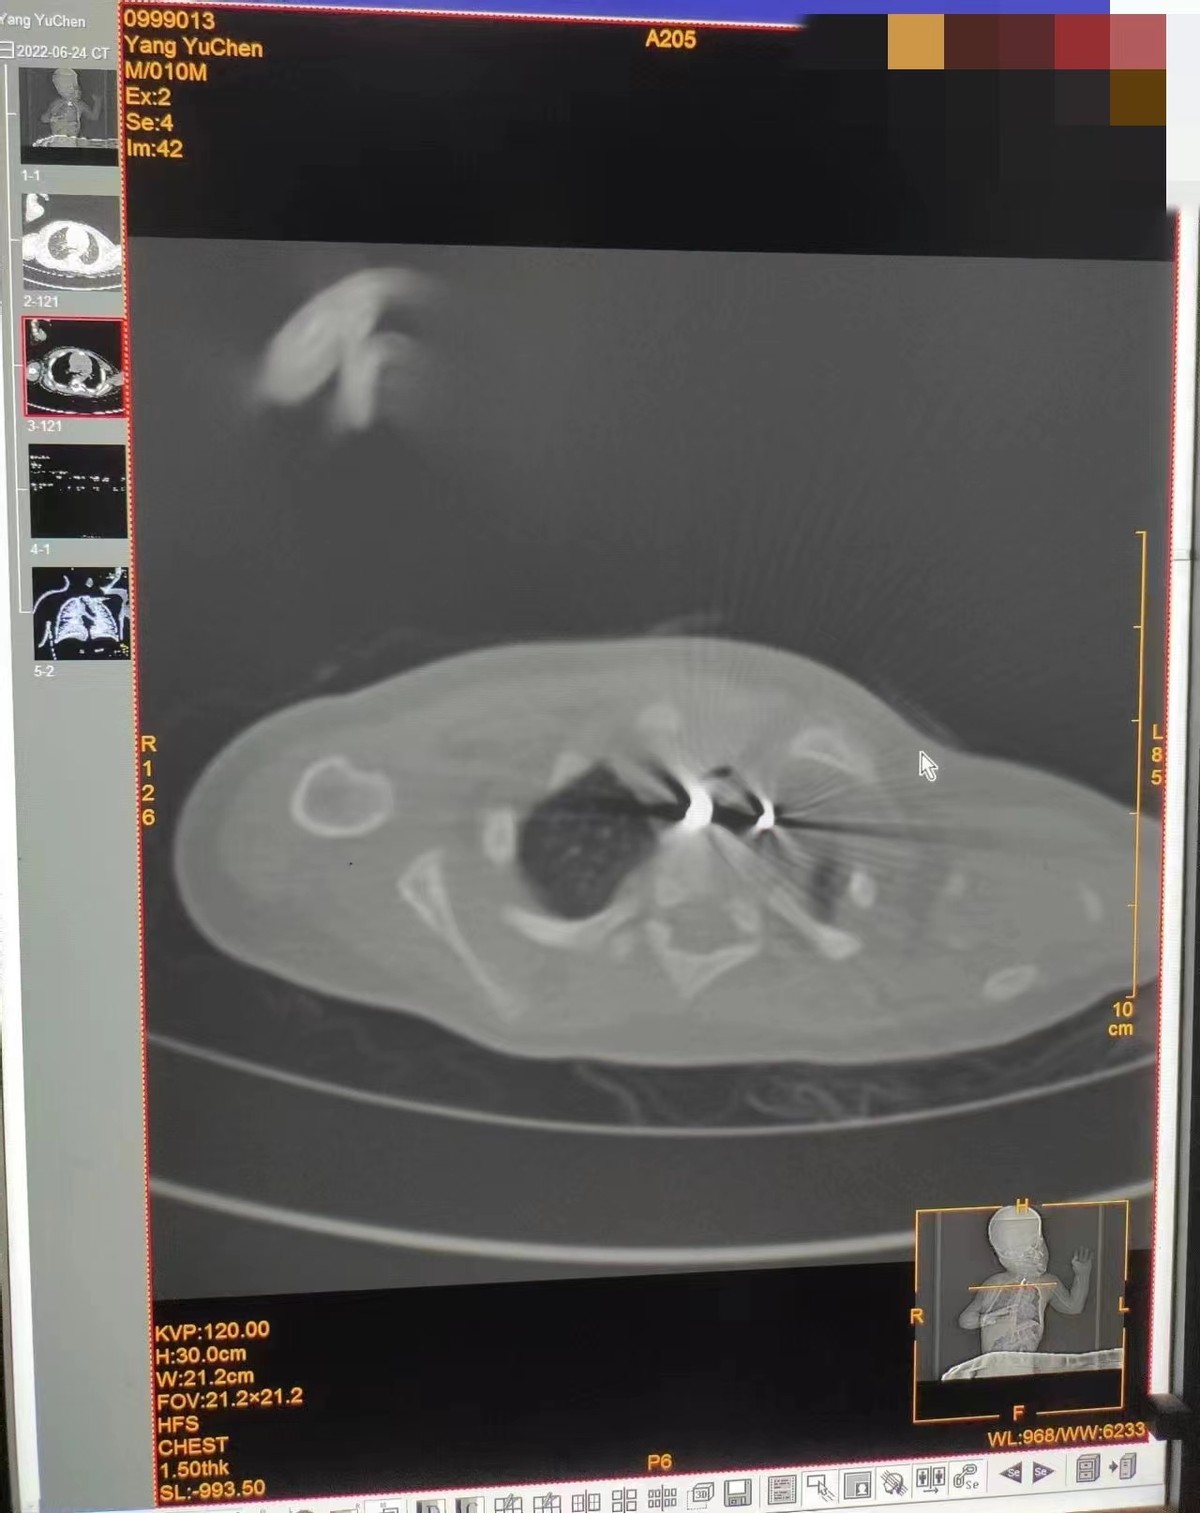

②待患儿入室后,侧卧于手术床上,连接心电监护仪,由鼻导管吸氧2L/min,而后缓慢静脉给与1.5-2mg/kg 1%丙泊酚,继续保留自主呼吸,缓慢置入胃镜,可见异物卡顿在食管第一狭窄处,远端扎入食道壁内,因粘膜水肿、空间窄、镜身活动受限,内镜医师经反复尝试后用异物钳钳夹异物取出,术中生命体征平稳,spo2维持在92%-99%,心率在100-110之间。若体动,追加丙泊酚0.5mg/kg。